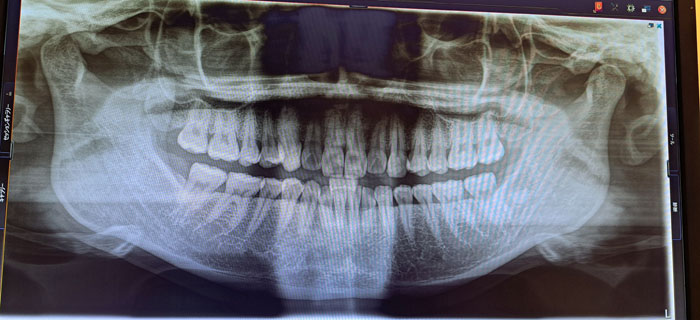

実際に矯正治療を行う前、私が通うクリニックでは「コンサルテーション」が必須で設けられていました。具体的には数種類のレントゲンや歯型取りをもとに、クリニックが提携する別の歯科医からも判断を仰ぐセカンドオピニオンのようなシステムで、それなりに時間もかかりますが、理にかなっているなあと。

というのも、データ採取から2週間後、別のクリニックから届いた診断結果には、シロウトでも解読できる日本語(ミミズがうじゃうじゃ並んだような判読不明のカルテとは異なる)で現在の問題点などが書かれていて、そのコピーを渡され、読みながら説明を受けると、疑問や不安の解消につながるのです。